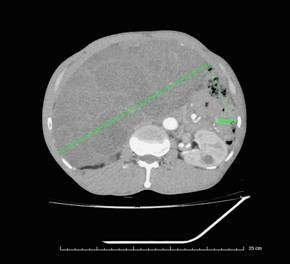

Quá trình chẩn đoán, qua chụp cắt lớp vi tính ổ bụng có hình ảnh khối u dạng đặc chiếm gần hết ổ bụng chủ yếu vùng bụng bên phải, chưa xâm lấn mạch máu lớn. Trên nội soi đường tiêu hoá thì khối u từ ngoài đẩy vào lòng đại tràng lên.

Khối u lớn khoang sau phúc mạc cạnh trước thận phải kích thước 233x191x141mm, bờ gọn, lan sang khoang cạnh trước thận trái, đè ép niệu quản phải gây giãn nhẹ đài bể thận phải, ngấm thuốc sau tiêm - Ảnh BVCC